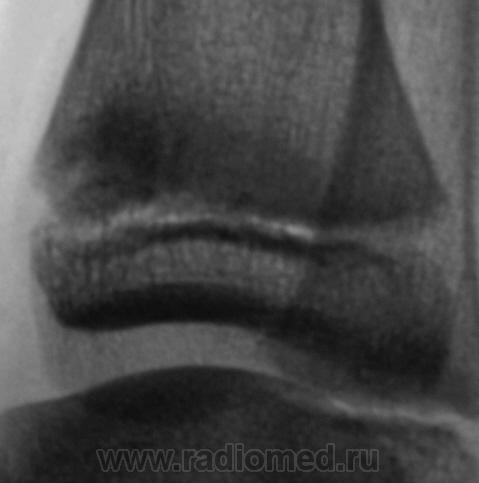

Травма. Пациент направлен хирургом на рентгенографию голеностопного сустава. Произведено стандартное исследование.

Уважаемый Валентин Львович! А что в жалобах, анамнезе? В переднемедиальной зоне дист. метафиза б/берцовой кости субхондрально под зоной роста участок уплотнения к/структуры, не отграниченный от неизмененной костн. ткани. Возможно, это импрессионный перелом? или остеонекроз? Смущает небольшой очаг аналогичной структуры в таранной кости под медиальным валом блока.

Клиника перелома. Травма - за 4 часа до исследования.

Согласен с коллегой helenmar по поводу перелома по типу импрессии, а ещё подвывих стопы в г/стопном суставе.

Травматических изменений не вижу

А как же объяснить асимметрию рентгеновской суставной щели?

Я тоже убедительных костно-травматических изменений не вижу. если есть сомнения, снимите вторую ногу.

А на мой взгляд, суставная щель вполне симметрична.

А, что, это за фрагментик?

У взрослого такие соотношения в суставе назову супинационным подвывихом, хотя прямая проекция не оптимальна для такого заключения, боковая вовсе косая.

Алё, детские рентгенологи! Уплотнение костной структуры над зоной роста патологическое или нет?

На мой взгляд, все указанные коллегами признаки - не патологические. Травматических повреждений нет.